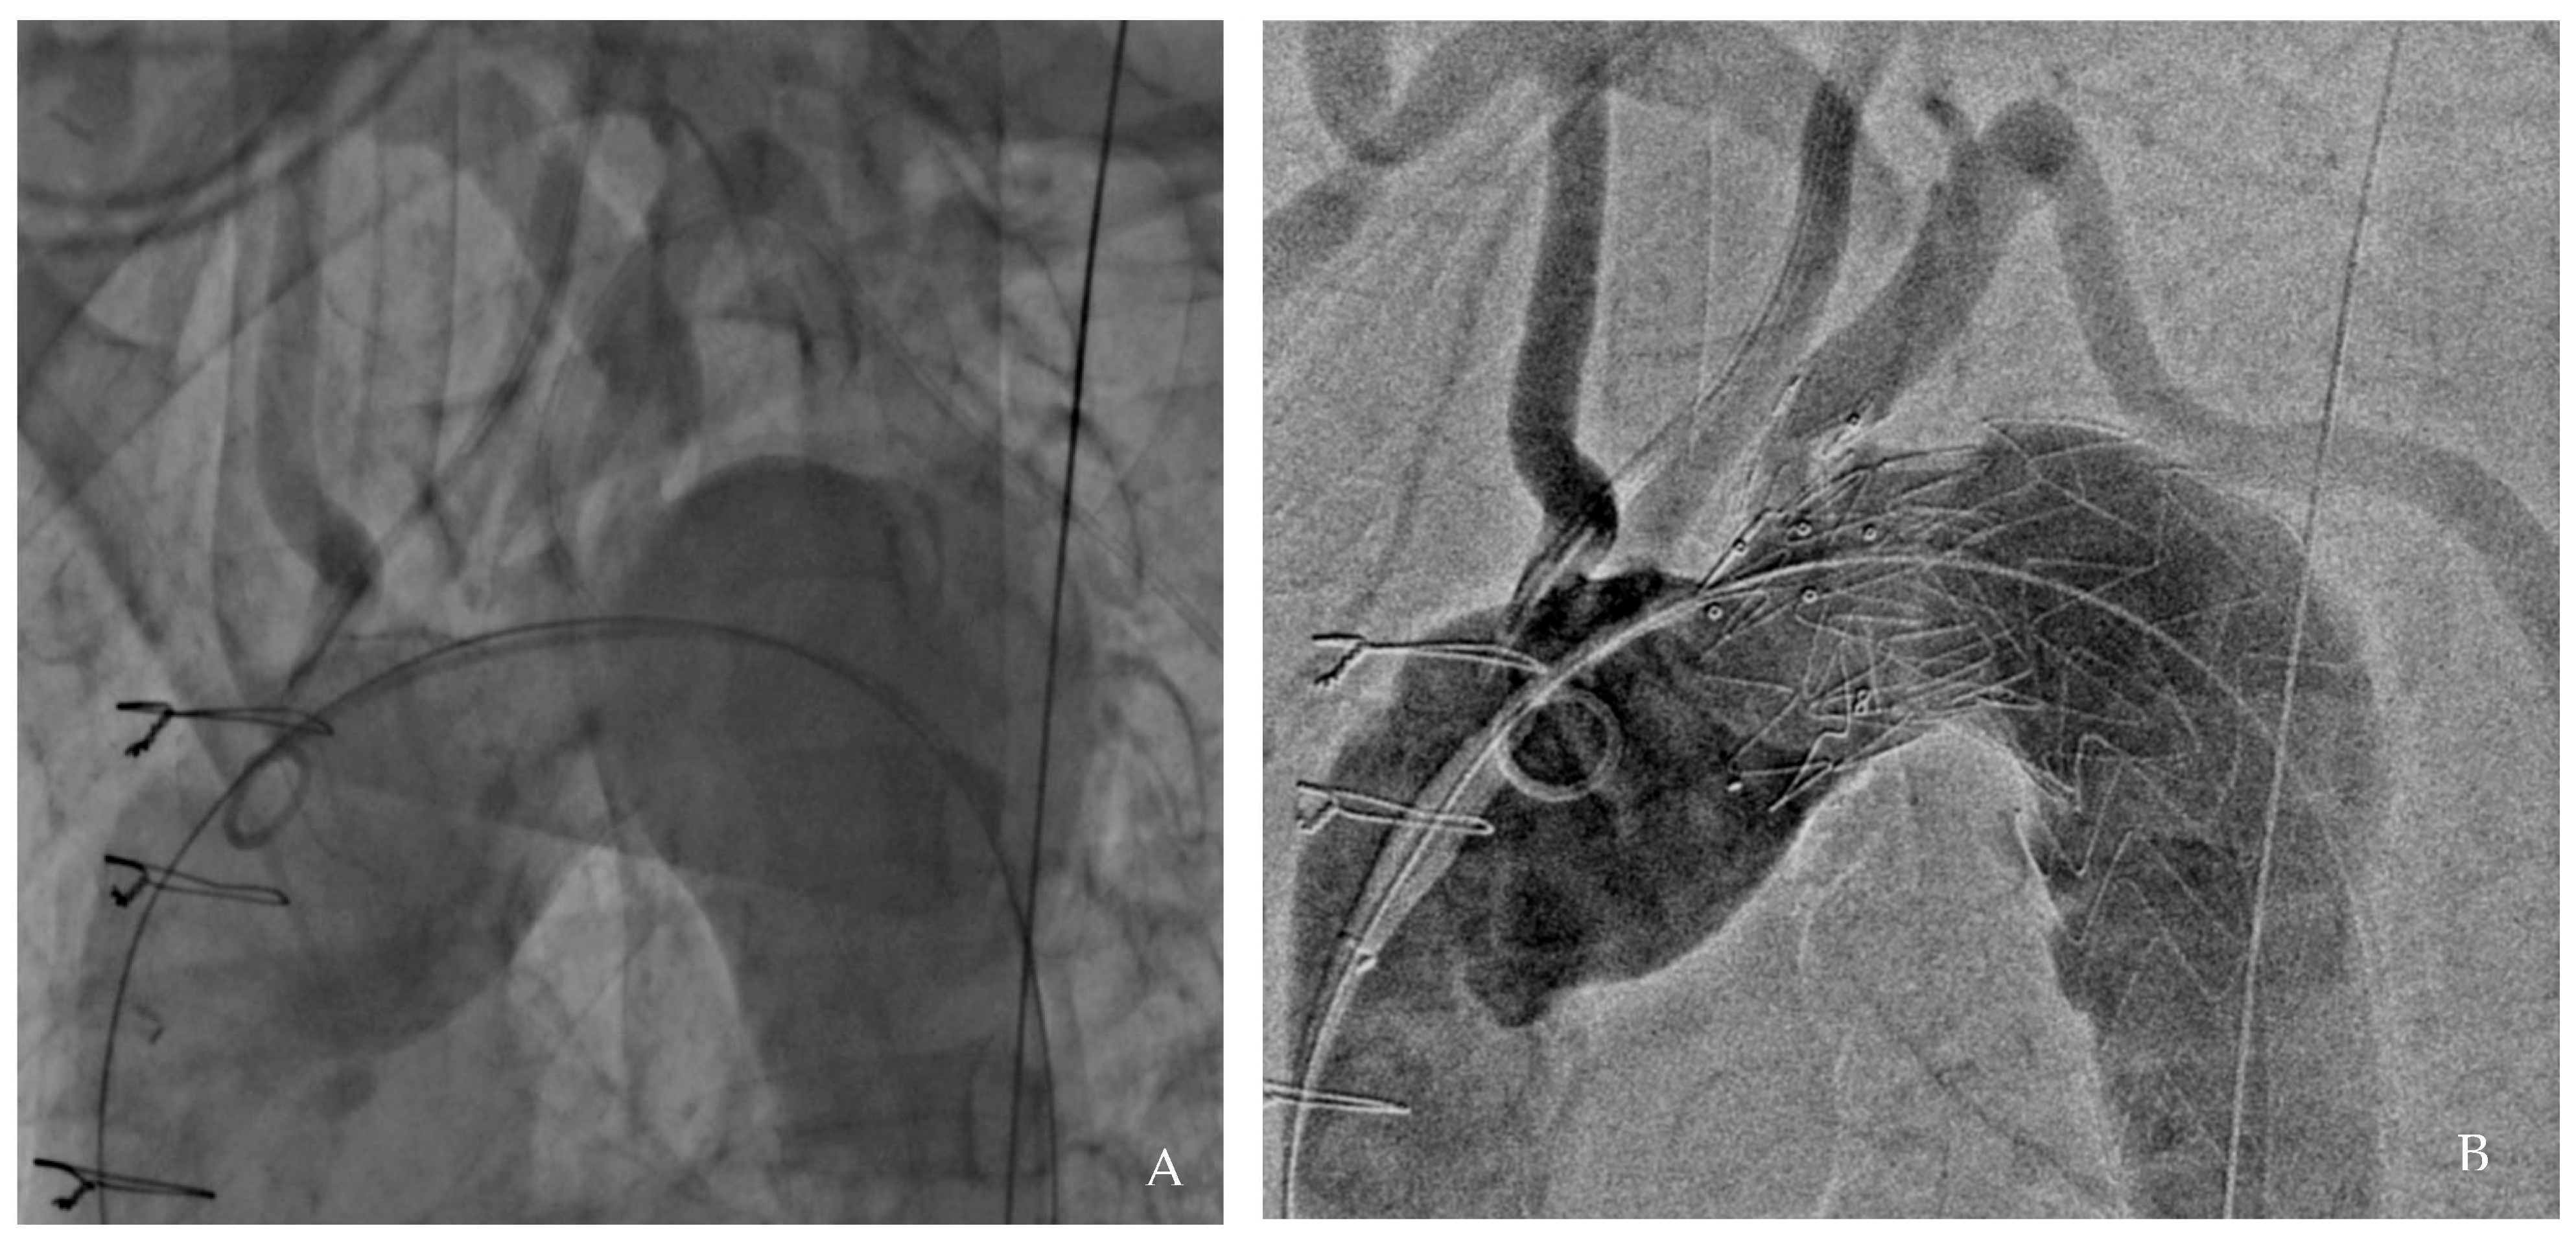

A final angiographic evaluation confirmed successful exclusion of the aneurysm and satisfactory perfusion of the supra-aortic vessels (Figure 2). The patient was discharged five days later on dual antiplatelet therapy (aspirin 100 mg and clopidogrel 75 mg) for three months, followed by lifelong aspirin monotherapy.

Figure 2. Angiographic results: pre-procedure (A) and post-procedure (B).